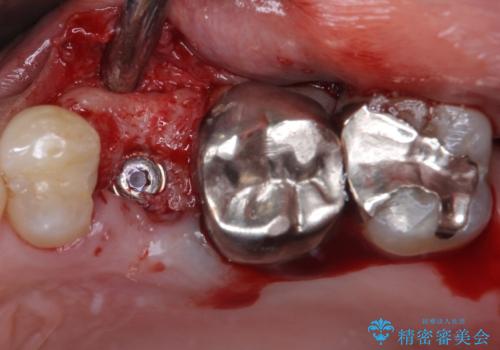

- 頻繁に銀歯が外れてしまうとのことで来院された患者様です。

歯肉の中、深いところまでむし歯が進行しており、歯根を部分矯正で引っ張り出してから補綴治療を行うか、抜歯してインプラント補綴治療を行うか選択することになりました。

海外での勤務があり、部分矯正は困難とのことで、インプラントによる補綴治療を行うこととしました。

より審美的で、より機能的に優れた治療をご希望とのことであったので、ジルコニアカスタムアバットメントを用いたインプラント治療を行うこととしました。

インプラントは、骨との生着能が比較的高いとさせるSLAタイプを使用しました。